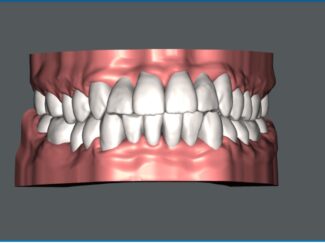

当院では、予防歯科を中心に一般歯科、小児歯科、インプラントや親知らずなどの口腔外科や

審美歯科(セラミック治療)、目立たない入れ歯や矯正歯科(マウスピース矯正)など、幅広く対応しています。